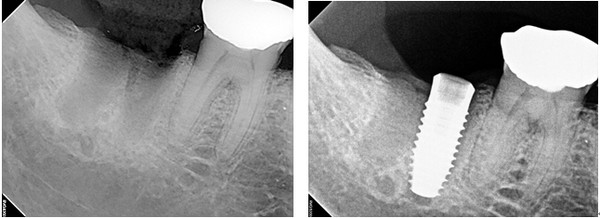

이성복 교수는 #47번 치아 발치 후 1개월이 경과한 시점에서 바로 가이드로 임플란트 식립을 위해 허영구 원장과 만남을 가졌다.

47번 대구치의 경우 2개의 치근으로 인해 발치와에 bony septum이 존재하고 발치와가 두 부분으로 나뉘어지면서 깊고 넓어 계획했던 3차원적 위치대로 임플란트 식립이 쉽지 않았다. 임플란트 식립을 위한 드릴링이나 임플란트를 식립하는 중에도 중심이 틀어져 정확한 식립이 어렵기 때문이다.

수술준비를 마치고 간단한 침윤마취가 끝나자 프리가이드 제작이 완료됐고 치은과 치조골의 치유 상태를 고려해 네오바이오텍 IT-III active Φ 5 x 11.5mm를 식립하기로 결정한 다음 바로가이드 키트로 임플란트 수술을 준비했다. 제작이 완료된 프리가이드는 식립위치와 방향에 맞게 정확히 환자의 구강내에 위치시켜 고정했다.

바로가이드를 사용해 임플란트는 계획된 곳에 정확히 식립됐고 식립토크는 40Ncm으로 측정돼 매우 안정된 초기 고정력을 기록했다. 수술은 계획한 시간 내에 완벽하게 완료됐다.